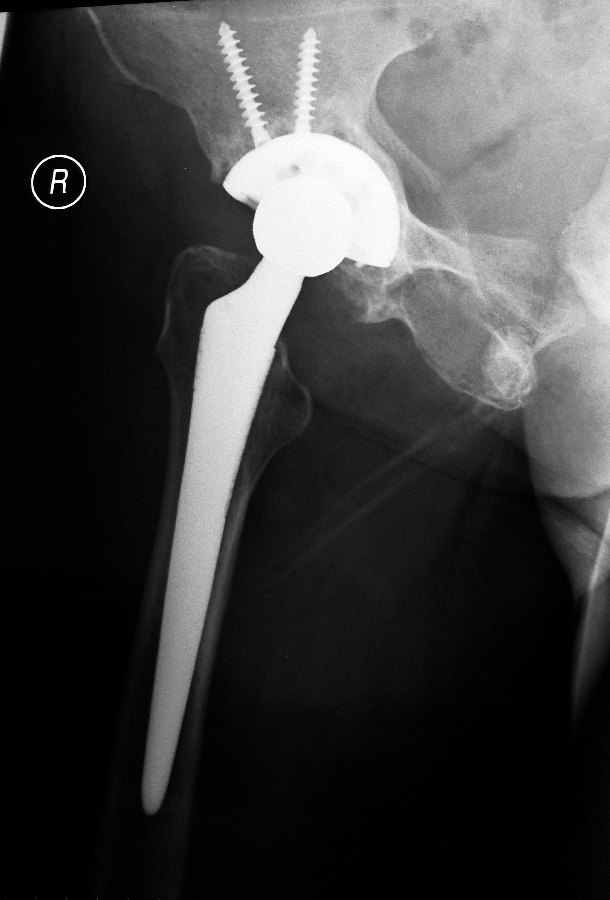

This is the post-operative x-rays showing the hip implants: